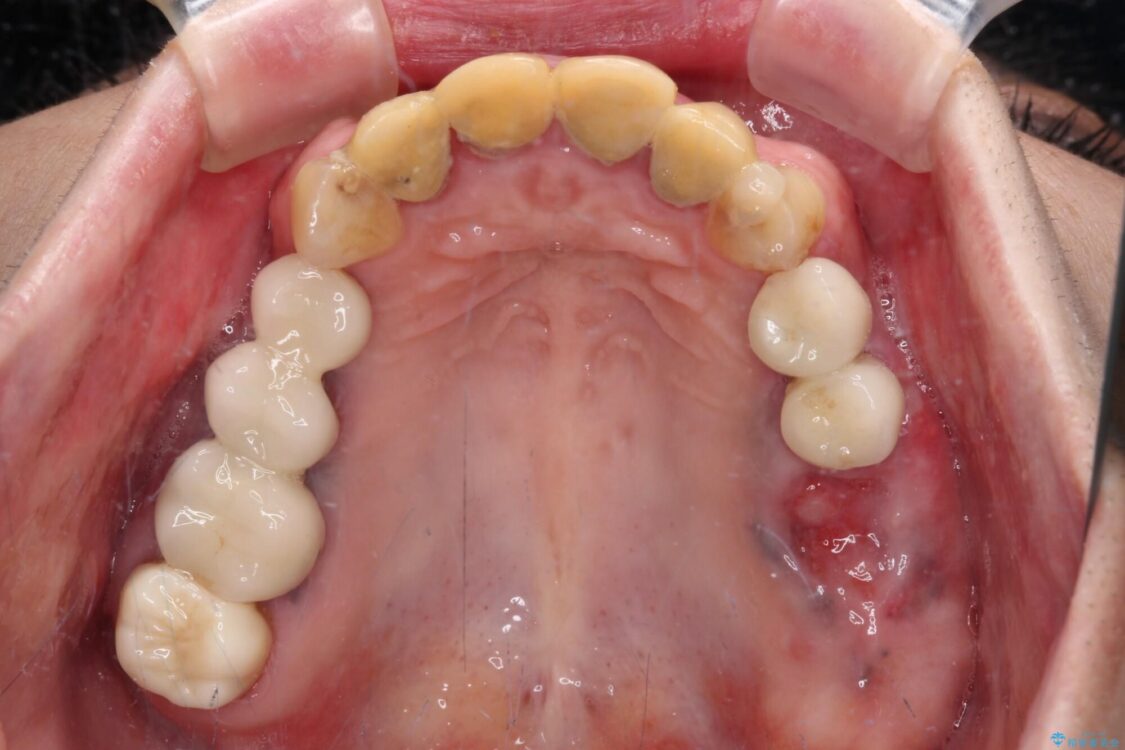

治療後

• 仮歯のまま放置した前歯 オールセラミッククラウンで自然な前歯に 治療後画像